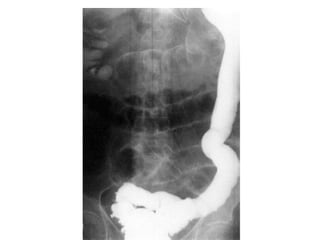

• Barium enema performed carefully may give the

diagnosis of colonic obstruction.

• Barium enema reveals a characteristic narrow segment.

• A full-thickness rectal biopsy will show absence of

• Large bowelobstruction with competent ileocecal valve show colon distention and little small bowel gas. • Large bowel obstruction with incompetent ileocecal valve shows small and large bowell distention and fluids levels. • Barium enema performed carefully may give the diagnosis of colonic obstruction. • At times is difficult to distinguish paralytic ileus from mechanical obstruction radiographically. • In paralytic ileus gaseous distention occurs uniformly in stomach, small bowel and colon. • In paralytic ileus gas-fluid levels may be seen. • Others investigations include: Serum electrolytes, Full hemogram, coagulation profile, renal function test, etc.

Hirschsprung’s disease: • Thisis due to failure of complete migration of the ganglion cells of the large bowel to the anus. • This results in an aganglionic segment producing physiological obstruction. • 80 per cent present in the neonatal period with acute large bowel obstruction. • 20 per cent present with failure to thrive or severe constipation. • Barium enema reveals a characteristic narrow segment. • A full-thickness rectal biopsy will show absence of ganglion cells. • Treatment consists of an initial loop colostomy followed by a definitive pull-through procedure.